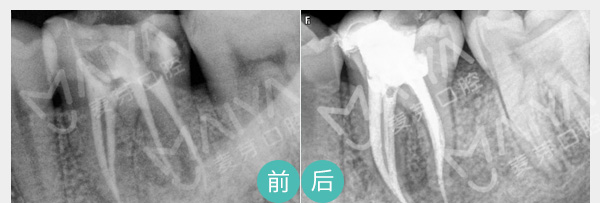

• 牙根疼痛、深度龋齿

麦芽显微根管治疗

通过机械和化学方法去除根管内感染物,通过充填根管、封闭冠部,防止发生根尖周病变或促进发生的根尖周病变的愈合。

适应症:深度龋齿